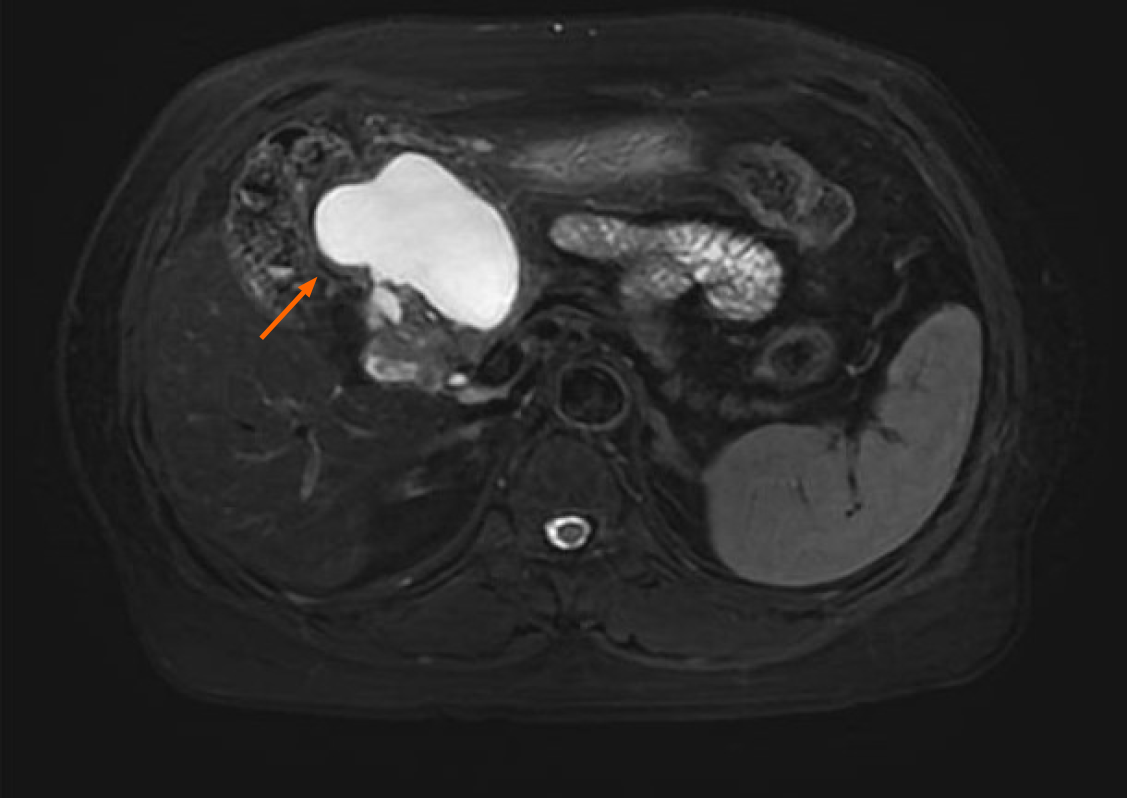

Contrast-enhanced abdominal computed tomography (CT) identified a cystic lesion in the right upper abdomen (Figure 1). This showed close anatomical relationships with both the pancreatic head and the greater curvature of the gastric antrum. An initial radiological assessment favored a benign pathology, with differential diagnoses including intestinal duplication and pancreatic cystadenoma. The subsequent pancreatic protocol magnetic resonance imaging with diffusion-weighted imaging (Figure 2) confirmed these findings but showed no evidence of malignancy.

An upper endoscopy revealed the following: (1) A large, soft submucosal lesion involving the pylorus and greater curvature of the gastric antrum, with preserved luminal patency; (2) An ulcerated lesion at the duodenal bulb-descending junction, with luminal narrowing and raised margins (Figure 3); and (3) Endoscopic ultrasonography (EUS) identified a 7 cm × 4.8 cm mixed cystic-solid mass with clear demarcation from the adjacent organs but a loss of interface with the fourth layer of the gastric wall (Figure 4).